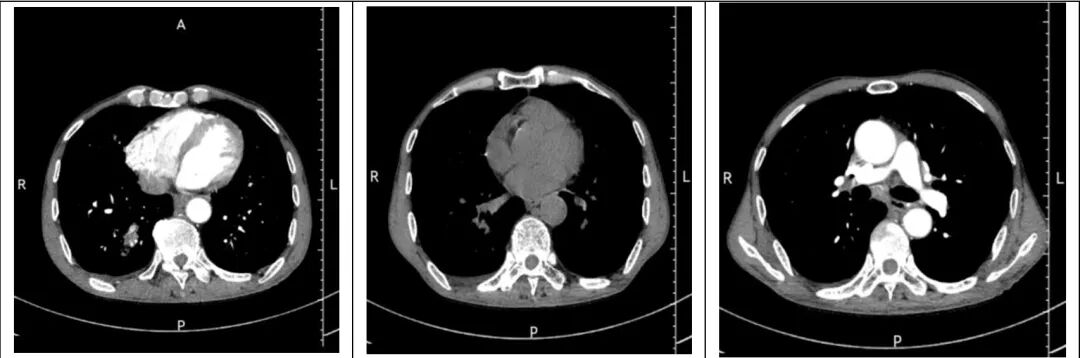

肺部CT:双肺炎症,右肺下叶团片状阴影;双肺微小结节及类结节;双肺纤维灶;纵隔及右肺门多发淋巴结;右侧少量胸腔积液;胸主动脉及冠状动脉钙化。见图1

▲图1

本例患者患有糖尿病,在10天前因受凉后出现咳嗽,咳痰,晨起加重,家中自行药物治疗,效果欠佳,偶咳整口鲜血,肺CT显示有炎症,结合BALF真菌培养及NGS结果示小孢根霉,最终考虑小孢根霉肺部感染形成团片状阴影,排除肿瘤可能。